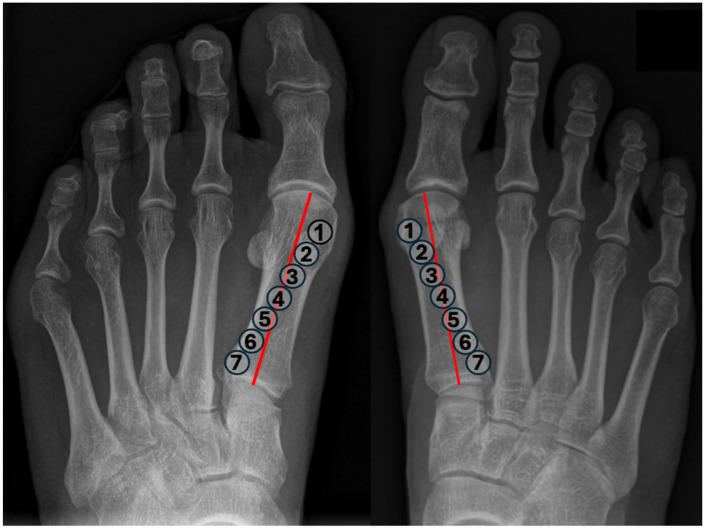

背景:第一跖骨旋转错位越来越被认为是拇外翻畸形的一个关键特征,但x线旋转标记物的可靠性仍然不确定。本研究评估了4个常用的影像学参数:跖骨旋前角(MPA)、胫骨sesamoid位置(TSP)、侧头形状(LHS)和圆头征象(RH)在观察者间和观察者内的可靠性。方法:在这项前瞻性可靠性研究中,3名资深临床医生独立评估了75例2次拇外翻的负重正位和轴位籽骨片。测量跖骨旋前角(MPA)作为连续变量,并使用类内相关系数(ICCs)进行分析。采用顺序量表对胫骨籽骨位置(TSP)、侧头形状(LHS)和圆头标志(RH)进行评分,并采用加权kappa统计量(κ)进行评估。亚组分析评估了可靠性是否因畸形严重程度(拇外翻角)或远端跖关节角(DMAA bbb10度)的增加而变化。结果:MPA具有良好的一致性(ICC = 0.81 ~ 0.94)。TSP也表现出高可靠性(κ = 0.88-0.98),尽管其作为旋转标记的价值有限。LHS具有中等至基本的一致性(κ = 0.59-0.85),而RH具有中等至中等的可靠性(κ = 0.35-0.66)。RH在轻度畸形中最不可靠,而其他参数在亚组中保持稳定,在DMAA升高的情况下值略低。结论:常规x线片可可靠评估MPA和TSP。LHS提供了可接受的再现性,而RH则不太一致。这些发现支持选择放射学标记物的使用,并表明针对三维成像和标准化分级框架的进一步验证可能会提高一致性和临床适用性。证据等级:四级,案例系列。

Background: Rotational malalignment of the first metatarsal is increasingly recognized as a key feature of hallux valgus deformity, but the reliability of radiographic rotation markers remains uncertain. This study assessed the inter- and intraobserver reliability of 4 commonly used radiographic parameters: metatarsal pronation angle (MPA), tibial sesamoid position (TSP), lateral head shape (LHS), and round head sign (RH).

Methods: In this prospective reliability study, 3 senior clinicians independently evaluated weightbearing anteroposterior and axial sesamoid radiographs of 75 hallux valgus cases on 2 occasions. Metatarsal pronation angle (MPA) was measured as a continuous variable and analyzed using intraclass correlation coefficients (ICCs). Tibial sesamoid position (TSP), lateral head shape (LHS), and round head sign (RH) were graded using ordinal scales and assessed with weighted kappa statistics (κ). Subgroup analyses evaluated whether reliability varied by deformity severity (hallux valgus angle) or increased distal metatarsal articular angle (DMAA > 10 degrees).